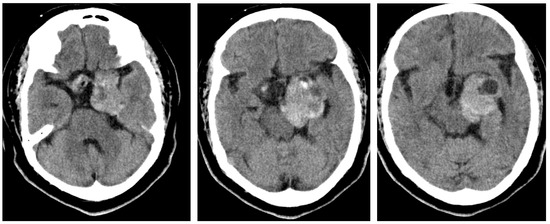

2.1. Case 1

2.2. Case 2